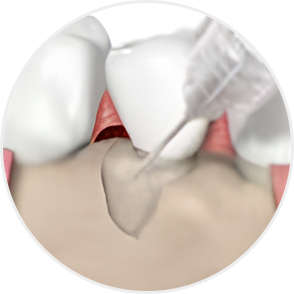

Emdogain Surgical Procedure

STEP 01

Gingival incision

STEP 02

Scaling and Root Planing (SRP)

STEP 03

Removal of calculus and plaque

STEP 04

Emdogain application

STEP 05

Cleansing

STEP 06

Flap closure and suturing